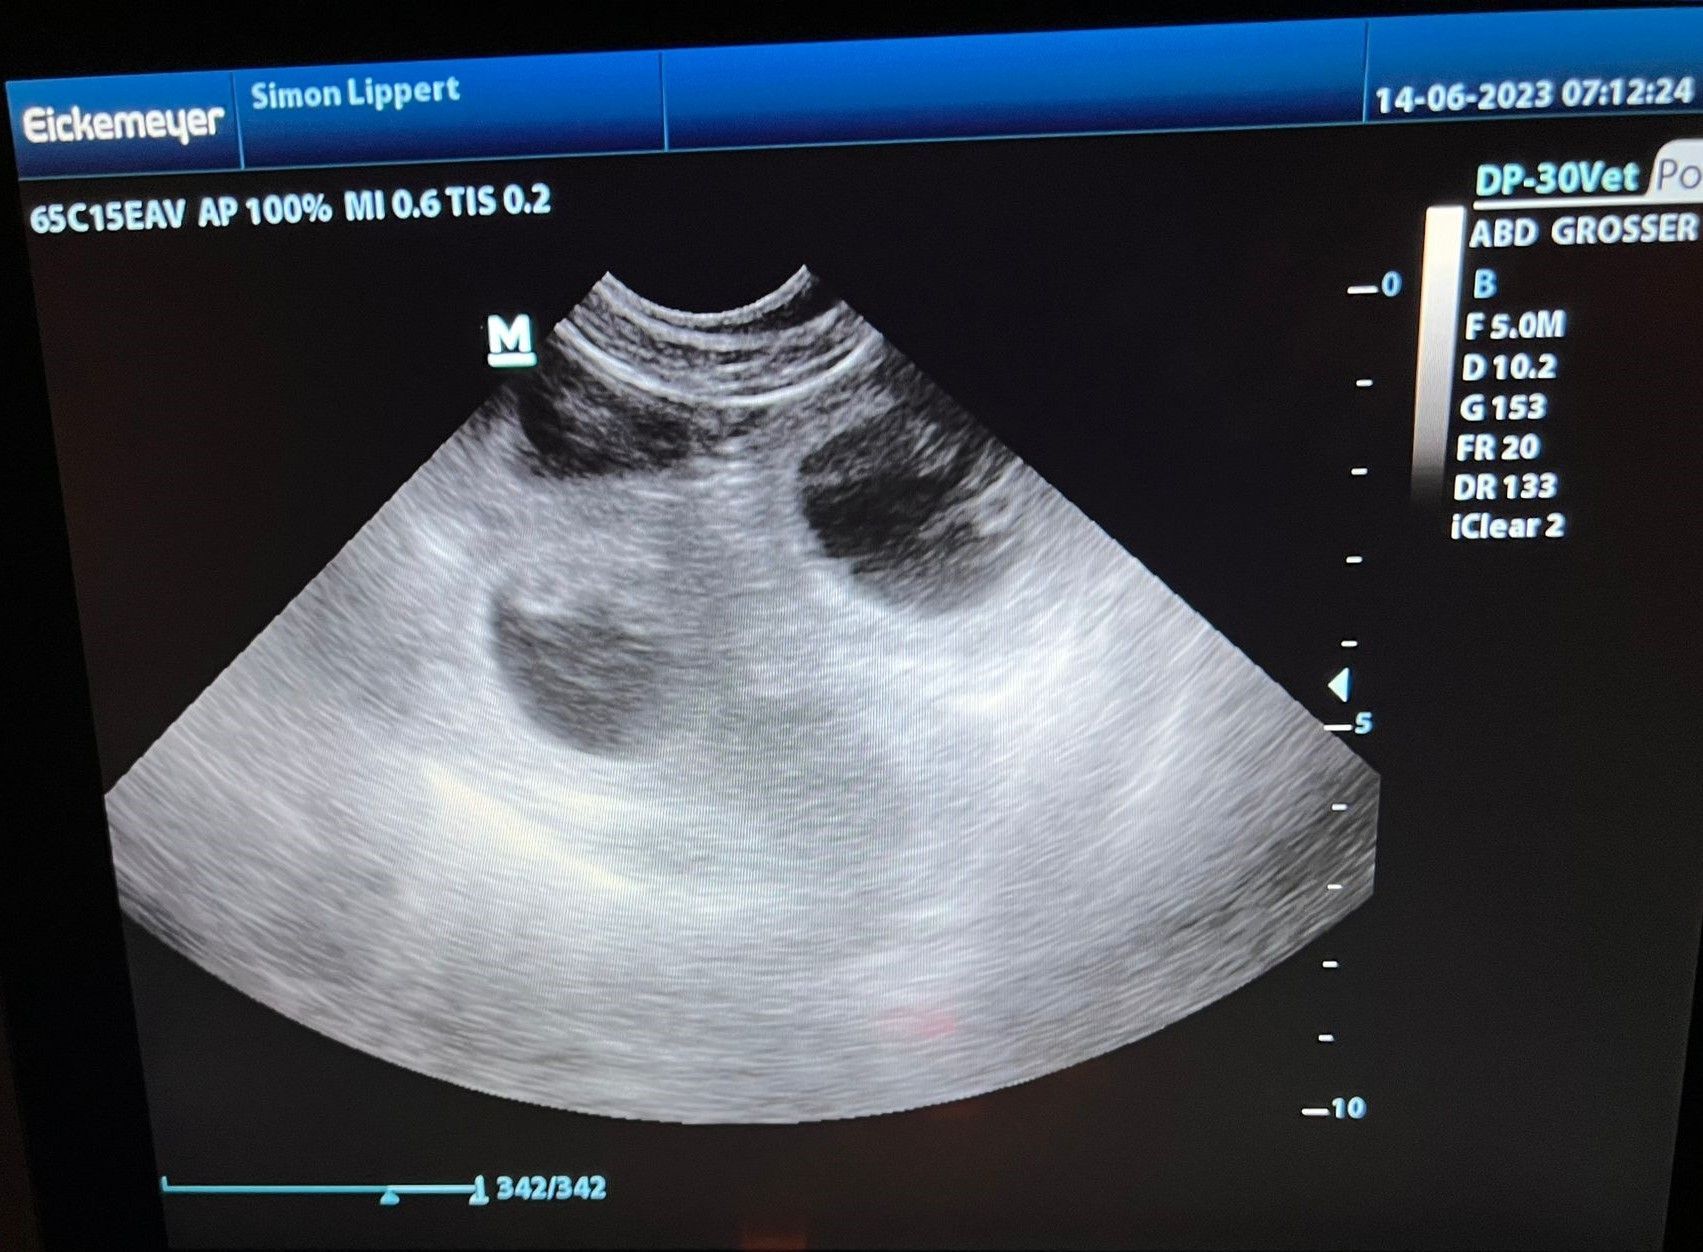

14.06.2023

Heute waren wir beim Ultraschall und sind voller Glück

BONNIE ist trächtig!!!